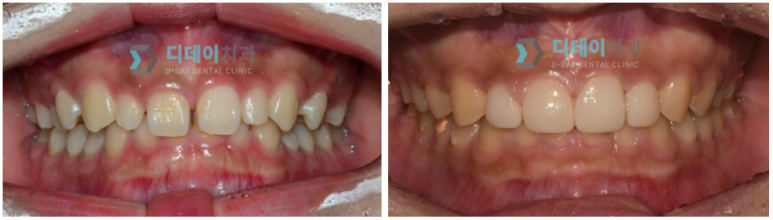

(전) 2021-11-20, (후) 2021-11-30

과도하게 자란 잇몸으로

치과용 레이저로 잇몸성형 진행

(전) 2022-02-14, (후) 2022-02-28

치아를 덮고 있는 잇몸라인을 높여주어

대칭을 맞춰준 모습

사진에서처럼 잇몸라인을 정리해 준 것만으로도 치아가 시원하고 커 보이는 것을 확인하실 수 있을 것입니다.